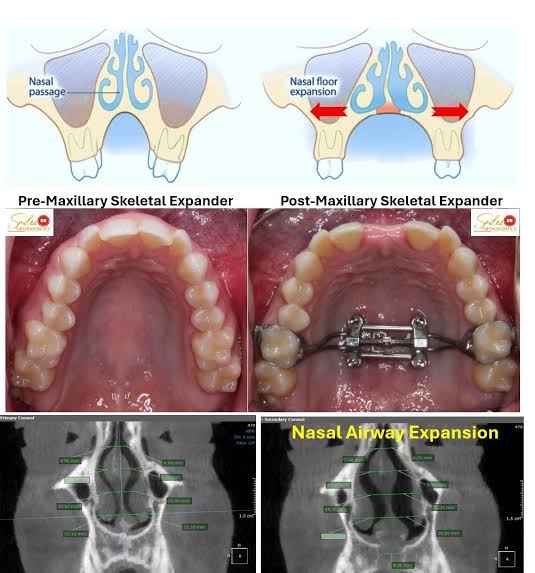

So he wore a face mask like below and had mse at the same time